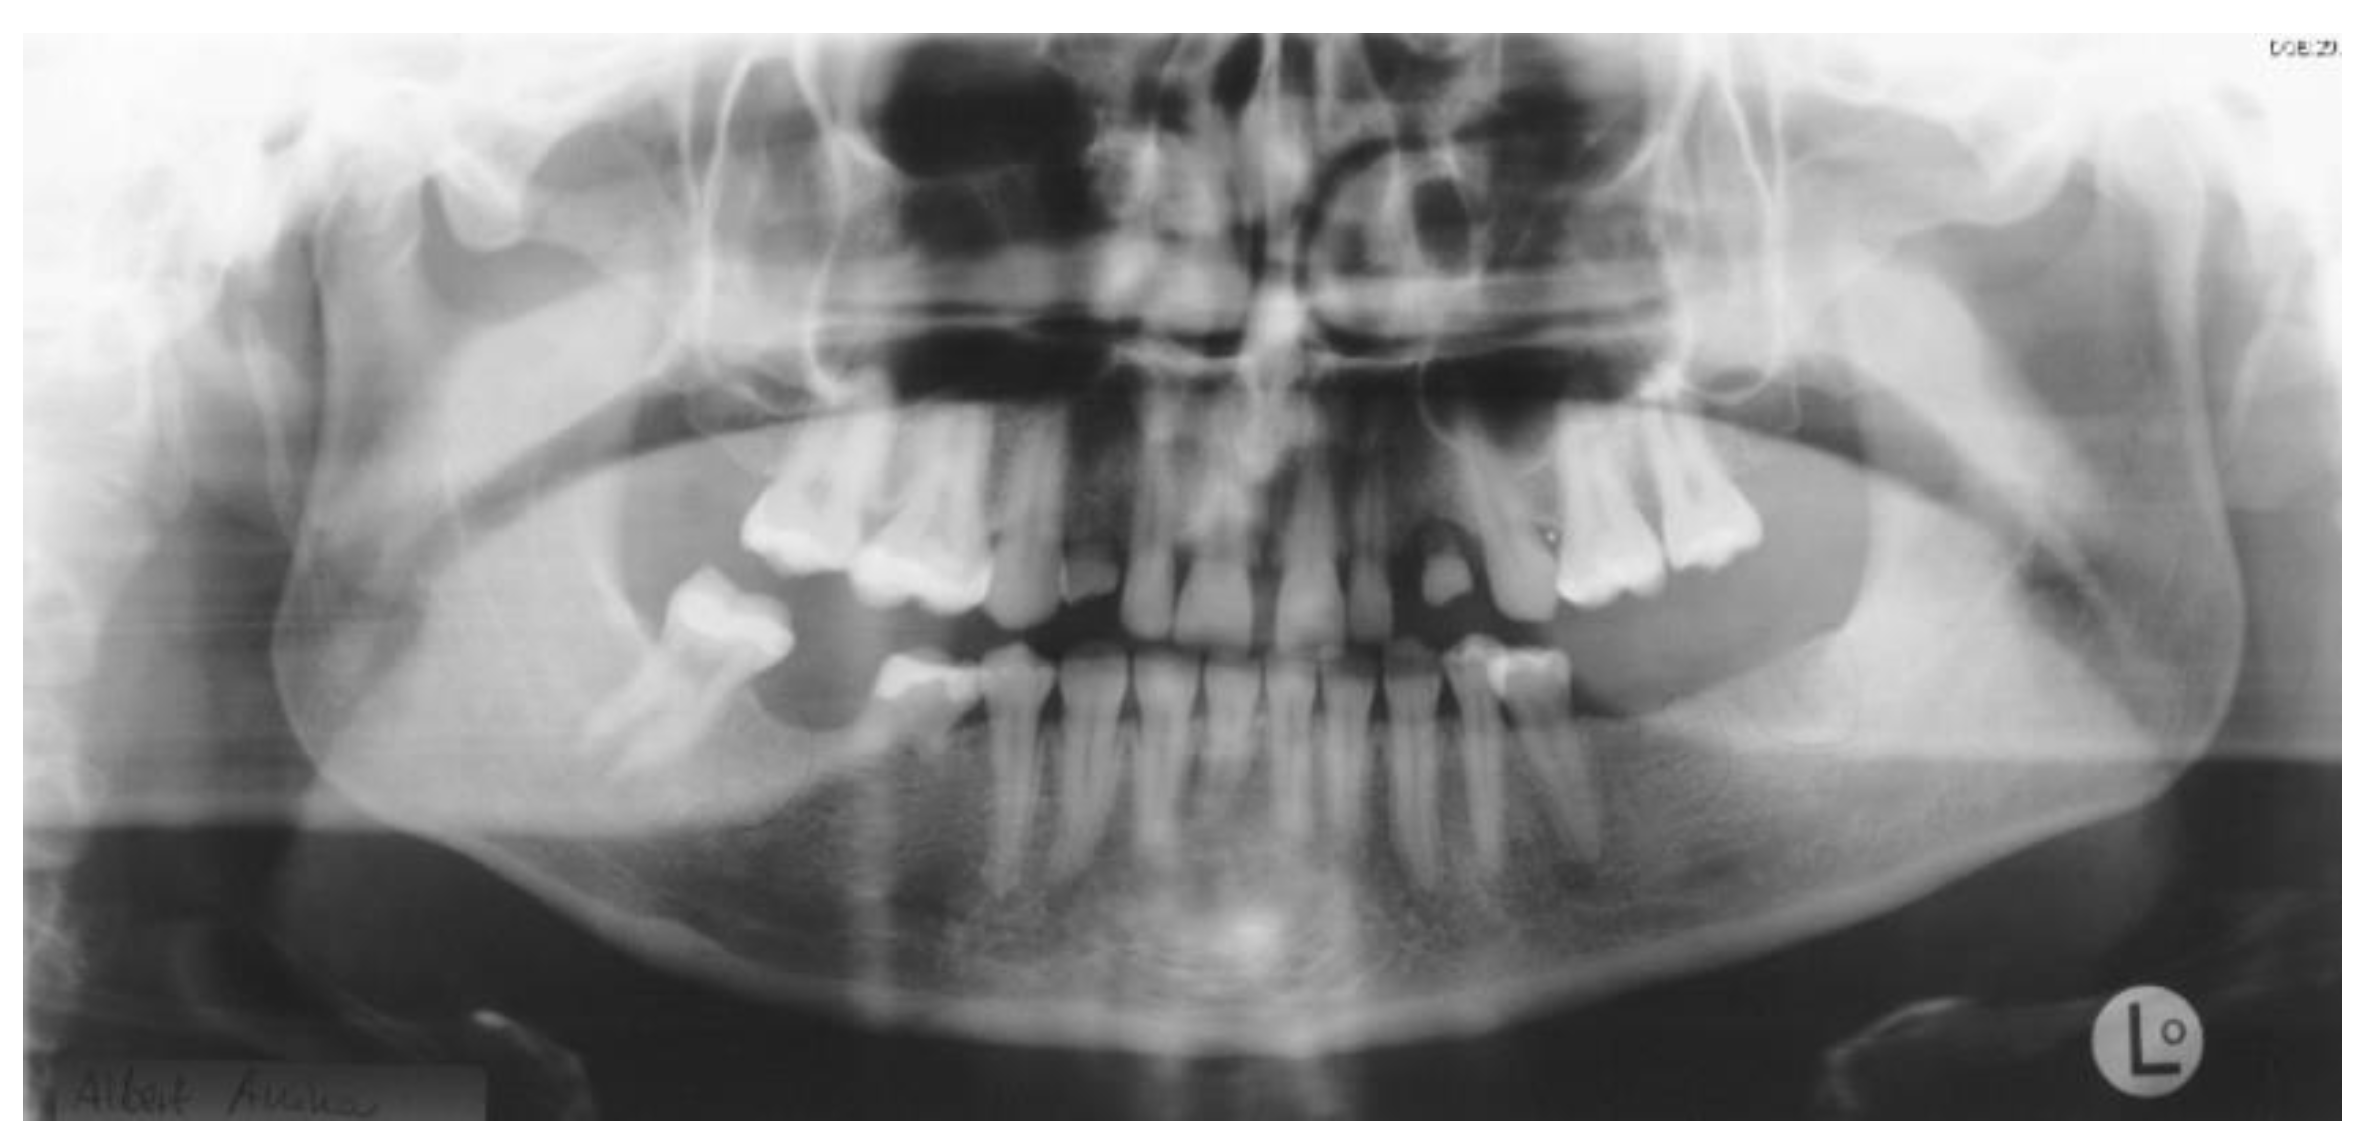

Figure 2.

Panoramic radiography after bone graft, nerve lateralization, and placement of dental implants in edentulous sites with adequate bone volume.

The first surgical procedure included nerve lateralization at the left lower jaw, sinus lift, and placement of dental implants in edentulous sites with adequate bone volume. In order to reduce the risk of nerve injury related to the exacerbated bone atrophy at left lower jaw, the placement of dental implants at the left site was planned digitally (Figure 2).